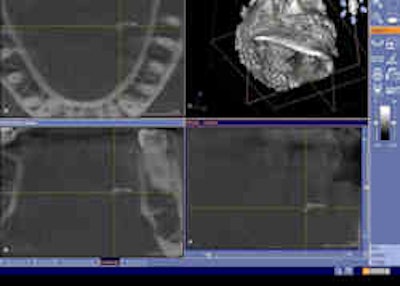

Cone-beam CT dataset showing a 2-mm salivary calculus in the left submandibular gland area in the axial (upper left), coronal (lower left), and sagittal (lower right) view. Clinical and conventional 2D diagnosis failed here due to the small size of the calculus. |

"Even the smallest calculi of 2 mm were visualized with the CBCT datasets," Dr. Dreiseidler stated in an e-mail to DrBicuspid.com. "In fact, standard resolution of CBCT datasets in general is higher than those of medical CT datasets. So, while the smallest voxel of cone-beam CT devices range from 100 to 300 microns, most commonly used medical CT protocols routinely have layer thicknesses of approximately 2 mm." That is why even the smallest salivary calculi can sometimes be depicted even better with cone-beam CT than with medical CT, he noted.